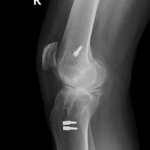

Your doctor will diagnose osteoarthritis based on the medical history, physical examination, and X-rays.

X-rays typically show a narrowing of the joint space in the arthritic knee.